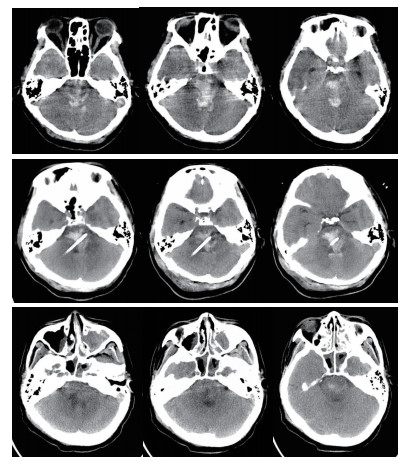

穿刺路径选择:行脑干出血立体定向穿刺分别采用幕上经额部及幕下经桥臂两种入路,笔者根据血肿的位置及患者的病情选择相应的入路,经幕上穿刺尤其适合侵及中脑的血肿,优点:体位摆放方便,对患者呼吸功能影响小,操作较简便,手术时间较短,血压监测较方便。缺点:穿刺路径较长,可能穿过脑室造成引流管移位,穿过丘脑及中脑,损伤损伤丘脑及中脑结构,如引流管置入过深可能损伤延髓。经幕下穿刺优点:经桥臂穿刺,穿刺路径短,损伤重要结构少,缺点:手术中需要侧卧位,可能影响呼吸,手术前应行气管插管,上头架时应预留手术穿刺位置,及耳环的位置,体位摆放及术中操作较复杂,手术时间较长。对于血肿侵及中脑或病情较重的患者,一般选择幕上经额穿刺(图 1)。如患者病情允许或术前有脑积水的患者,一般选择经幕下经桥臂入路,并根据血肿形态使引流管纵行穿过血肿(图 2)。

| 图 2 经幕下入路脑干血肿穿刺A:血肿穿刺前B:血肿穿刺后复查C:穿刺后6 d复查 |

本组手术术后24 h内血肿大部排空有7例,24~48 h大部排空有11例,48~72 h大部排空8例(图 1,2)。于1~4 d内拔除血肿腔引流管。术后8例患者3个月内死亡,死亡率25.8%。1例术中突发血压持续降低后,术后弥漫性脑肿胀死亡。1例术前吸入性肺炎严重,术后感染性休克死亡。1例肝功能不全,术中术后反复出血,家属放弃治疗死亡。1例术后不明原因高热,消化道出血,家属放弃治疗死亡。2例术后突发呼吸心搏骤停死亡。2例术后再出血,家属放弃治疗死亡。18例于术后3个月内清醒,均留有不同程度残疾,5例3个月内未清醒,存活病例随访3个月至1年后,格拉斯哥结局量表(GOS) 5级5例,4级7例,3级6例,2级5例,1级8例。植物状态及死亡患者多为出血量大(>10 mL),术前昏迷程度较深的患者(GCS评分3~5分)。